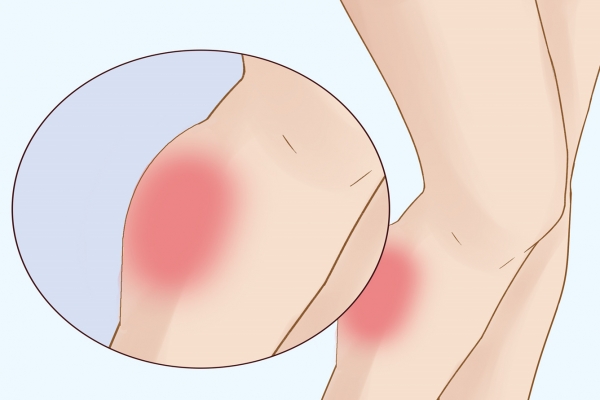

2.肿胀和淤青

拉伤后,受损部位可能会出现肿胀,尤其是中度和重度拉伤时,血液渗出会导致皮肤下出现淤青。淤青的颜色可能从红色逐渐变为紫色、蓝色,最后变成黄色或绿色。

5.局部发热

由于炎症反应,受伤部位的皮肤温度可能会升高,触摸时感觉比周围皮肤更热。